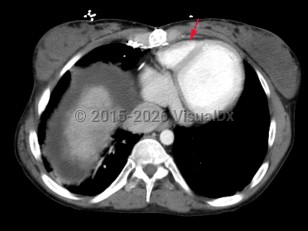

Imaging Studies image of Tricuspid atresia - imageId=6847804. Click to open in gallery.  caption: '<span>Axial CT image of the chest  demonstrates a hypoplastic right ventricle consistent with patient's history of congenital  tricuspid atresia.</span>'

Axial CT image of the chest demonstrates a hypoplastic right ventricle consistent with patient's history of congenital tricuspid atresia.